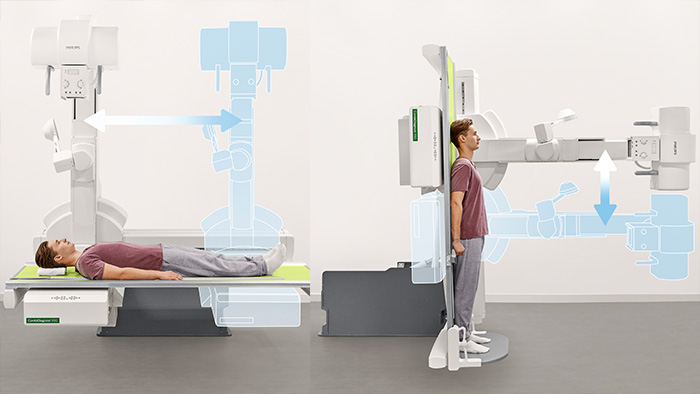

The orthopedic package is designed to allow you to do full spine and full leg imaging either on the vertical stand (equipped with the patient support), or simply at the table for lying or standing patients. Systems which are already configured with automatic image stitching at the vertical stand can now experience enhanced room flexibility by adding the automatic image stitching software for images acquired at the CombiDiagnost R90 table.

Highlights of the package*

Patient comfort

Flexible workflow

Fully automatic